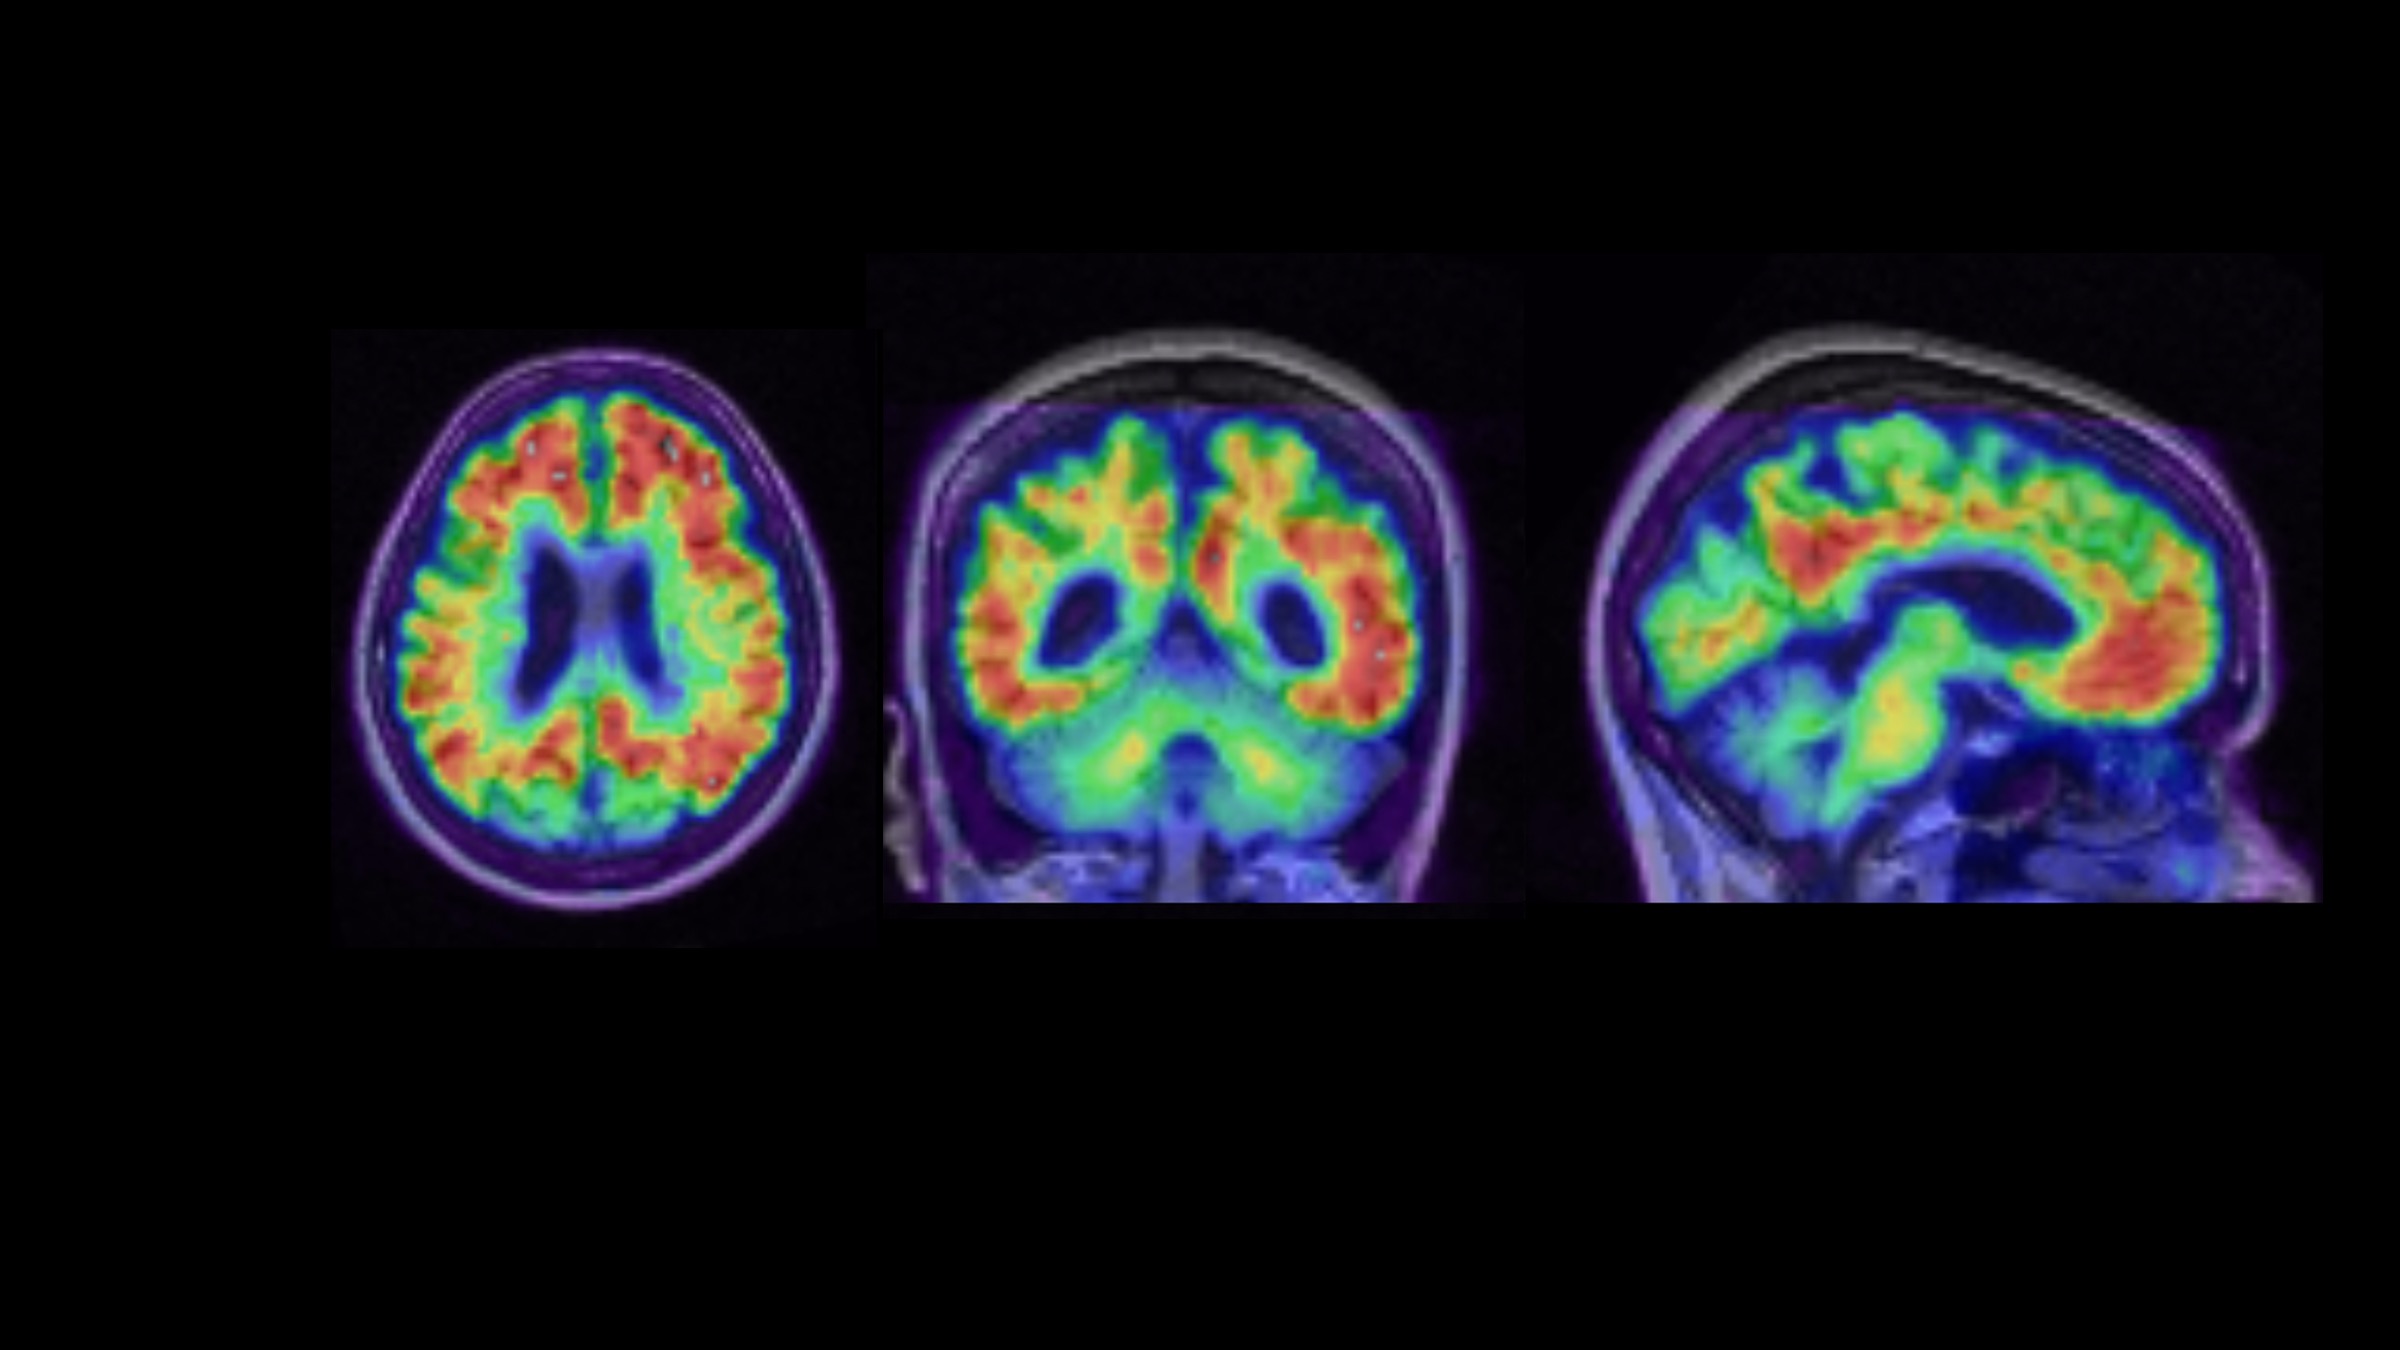

Neurodegenerative disease research

Combining cell and tissue imaging and neuroscience to improve our understanding of the anatomical, biochemical, and neurochemical underpinnings of neurodegenerative diseases.

Brain aging and dementia

Studying normal brain aging processes and neurodegenerative disease pathology using positron emission tomography (PET), structural magnetic resonance imaging (MRI), functional magnetic resonance imaging (fMRI), neuropsychology, and cognitive neuroscience.